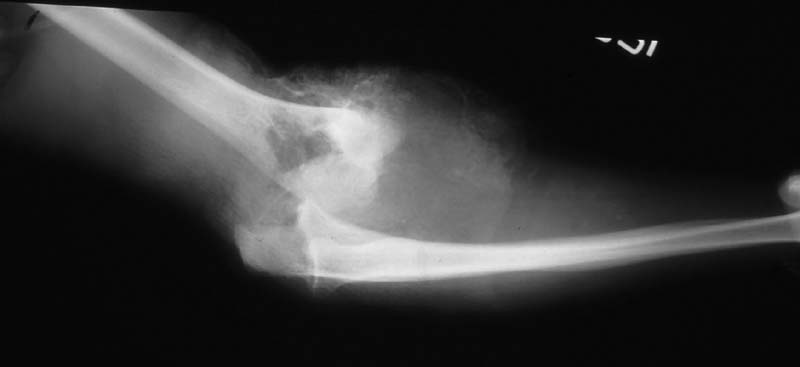

Case 2 - avulsed elbow joint with complete pulling apart of brachial artery, open wound with huge overlying skin loss. Immediate OR, brachial artery shunted, THEN Ortho puts on cross-joint ex-fix, we come back and definitively repair artery (ASVG), document patency with on table completion angio--then plastics swings lat dorsi pedicled flap thru axilla to cover.

Initial xray

Completion angio